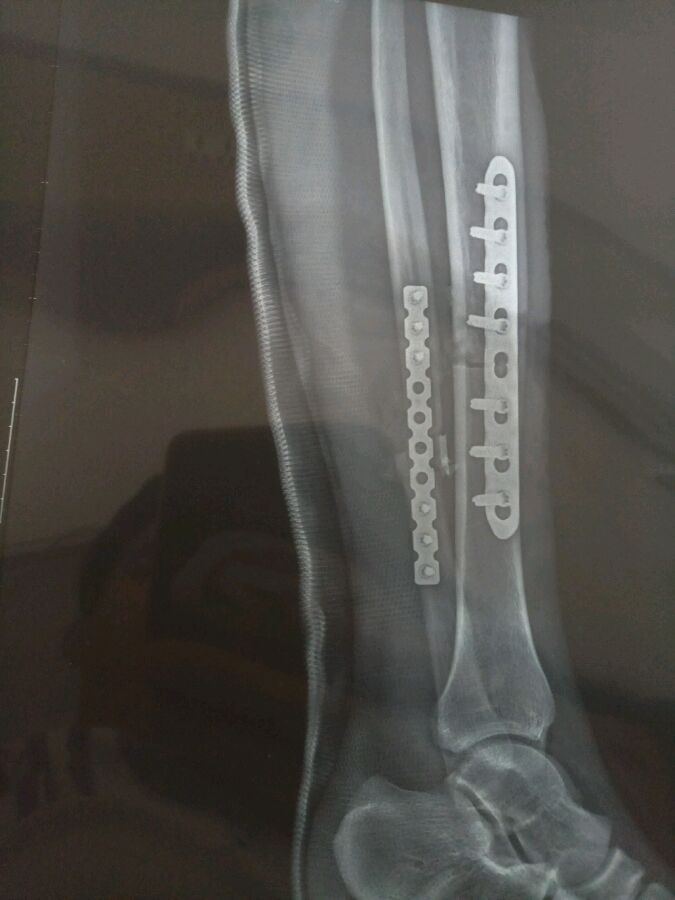

车祸受得伤,现在做完手术了。医生说我粉碎性骨折缺骨有点严重,有可能不能恢复!有没有相同情况的病友!这两个骨头能长好么?我女朋友都还没有,我不想残废呀!

看片子确实听严重

不过看你手术做的确实不错,固定的很好

不会残废 胫骨能长好 腓骨基本要植骨 腓骨不是主要承重骨 问题不大 你现在问医生 能不能做康复训练 这样能刺激骨痂生长